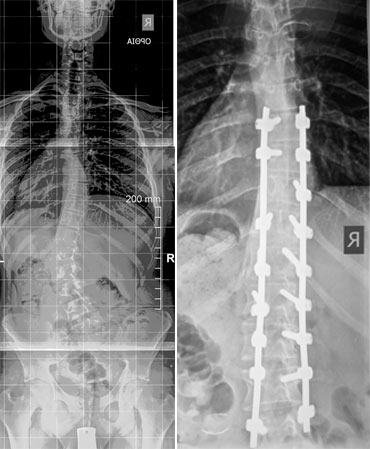

Για πρώτη φορά στην Ελλάδα εφαρμόστηκε με απόλυτη επιτυχία, στο Metropolitan Hospital (06/06/2016) η χειρουργική πλοήγηση σε νεαρό κορίτσι με ιδιοπαθή σκολίωση.

Η επέμβαση πραγματοποιήθηκε με απόλυτη ασφάλεια και ακρίβεια χάρη στη διεγχειρητική πλοήγηση, ενώ το αισθητικό αποτέλεσμα κρίθηκε ως άριστο από την ίδια την ασθενή αλλά και την ιατρική ομάδα.

Η χρήση του μέχρι σήμερα περιορίζονταν σε παθήσεις ασθενών μεγαλύτερης ηλικίας. Η χρήση του σε παιδιά ήταν η πρώτη για τα ελληνικά ιατρικά δεδομένα. Ο Δρ. Μάριος Λυκίσσας, χειρουργός με εξειδίκευση στις παθήσεις της σπονδυλικής στήλης έχει χρησιμοποιήσει το σύστημα της πλοήγησης σε παιδιά αλλά και ενηλίκους στις ΗΠΑ, αλλά όπως δήλωσε ο ίδιος, αυτή ήταν η πρώτη φορά που χρησιμοποίησε το σύστημα αυτό σε νεαρό ασθενή με σκολίωση στην Ελλάδα. Σύμφωνα με τις δηλώσεις του, “…το σύστημα αυτό πέραν της απόλυτης ασφάλειας στην τοποθέτηση των εμφυτευμάτων εξασφαλίζει και ένα εξαιρετικό αισθητικό αποτέλεσμα, πράγμα ιδιαίτερα σημαντικό για της νέες κοπέλες που πάσχουν από ιδιοπαθή σκολίωση.”